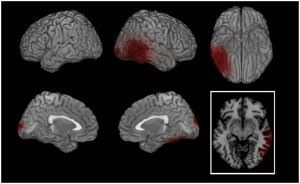

How Brain Response to EMDR Therapy

Credit picture: insidethealcoholicbrain.com

(จากภาพจะเห็นได้ว่า PTSD ที่เป็นสีแดงหลังทำจิตบำบัดEMDR ได้มีแสดงภาวะPTSD ลดลงและย้ายไปอีกฝั่งหนึ่งและหายไป เป็นผลสำเร็จในการรักษาPTSD ปมบาดแผลทางใจ)

การแก้ไขให้สมองได้มีการจัดเก็บประมวลผลใหม่ให้เสร็จสมบรูณ์นอกจากจะช่วยลดความทรงจำอันเจ็บปวดแล้วยังสามารถช่วยฟื้นฟูประสิทธิภาพด้านความคิด การควบคุมอารมณ์ การนอนหลับ หรือปัญหาสุขภาพทางร่างกายอื่นๆที่มีสาเหตุมาจากปมบาดแผลทางใจและทำให้แสดงออกแบบผิดปกติทางร่างกายต่างๆ ดังนั้นการรักษาช่วยให้เกิดการฟื้นฟูทั้งด้านร่างกายและจิตใจทำให้กลับมาใช้ชีวิตได้อย่างมีความสุขต่อไป